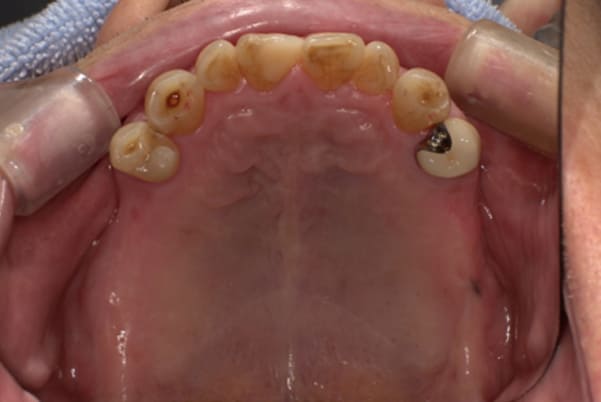

上顎治療前

根のみの7本は虫歯にもなっており歯肉は腫れあがっています。

残りの歯もレントゲンで重度の歯周炎によりぐらぐらな状態でした。